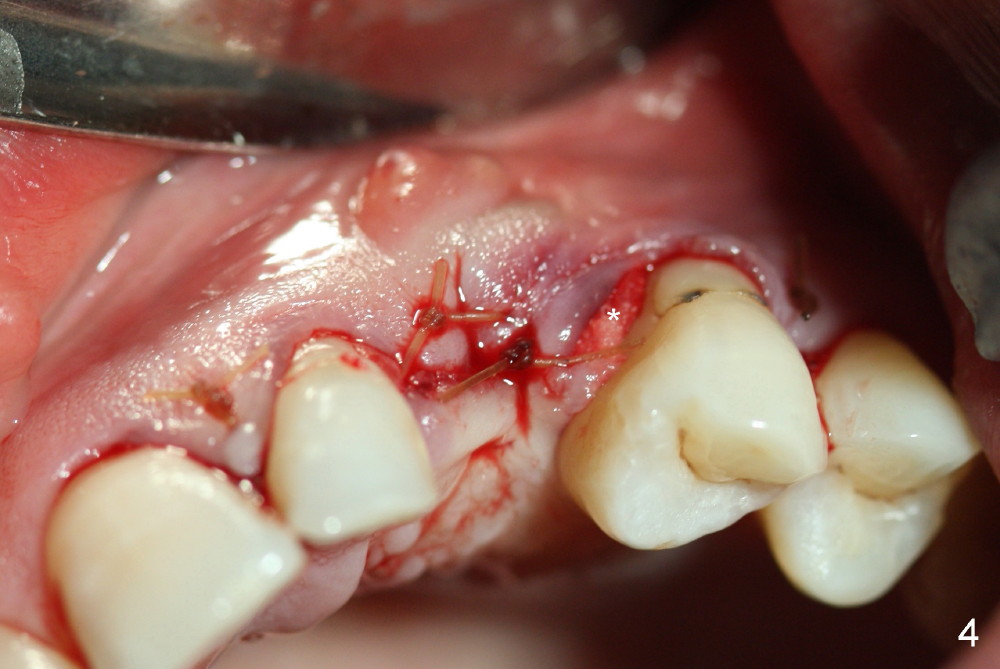

Repair of Buccal Plate Associated with Implant Failure

One month post-implantation at the site of the upper left deciduous canine, the patient returns for follow-up with chief complaint "The crown is a little loose. A bubble is becoming smaller". Exam shows an abscess (Fig.1 <) above the provisional (#11). The provisional is loose with mild tenderness. A pull on the provisional leads to dislodgement of the abutment and implant. Raising the buccal flap reveals perforation of the buccal plate with granulation tissue (Fig.2). After debridement (Fig.3), allograft and Osteogen is placed in the defect, followed by Osteotape (Fig.4 *) and suture. This complication can be prevented by CT information. A deciduous tooth socket is small. The immediate implant should be not too large, leaving 2 mm buccal gap. Three months 20 days post graft, the ridge looks not so atrophic (Fig.5). There is no sign of bone resorption (Fig.6). The patient will return for implant placement for the second time soon. Measure the bone width with bone caliper after local anesthesia. Fully expose the alveolus. Start osteotomy as palatal as possible. Repeatedly check osteotomy position and trajectory. Use surgical stent. The implant will not be too long or too wide. Is the ridge as wide as clinically shown?